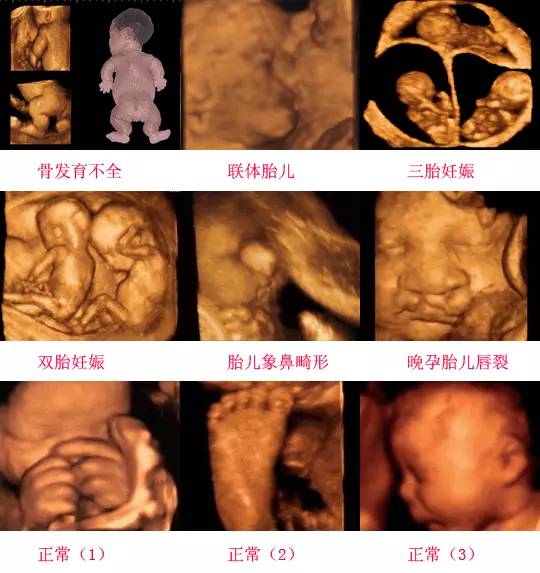

在四維彩超下,胎兒蛋蛋呈現(xiàn)出特定的形態(tài)和外觀,通常情況下,胎兒蛋蛋呈現(xiàn)出圓形或橢圓形,表面光滑,內(nèi)部回聲均勻,隨著胎兒的發(fā)育,蛋蛋會逐漸增大,并呈現(xiàn)出明顯的性別特征,醫(yī)生可以通過四維彩超技術(shù),對胎兒蛋蛋的大小、形態(tài)和位置進行評估,以判斷胎兒生殖系統(tǒng)的健康狀況。

四維彩超技術(shù)在評估胎兒蛋蛋發(fā)育方面具有重要意義,通過四維彩超,醫(yī)生可以實時觀察胎兒蛋蛋的形態(tài)、位置和大小等特征,了解胎兒生殖系統(tǒng)的發(fā)育情況,四維彩超還可以幫助醫(yī)生發(fā)現(xiàn)可能的異常情況,如睪丸未降、睪丸囊腫等,為及時采取治療措施提供依據(jù)。